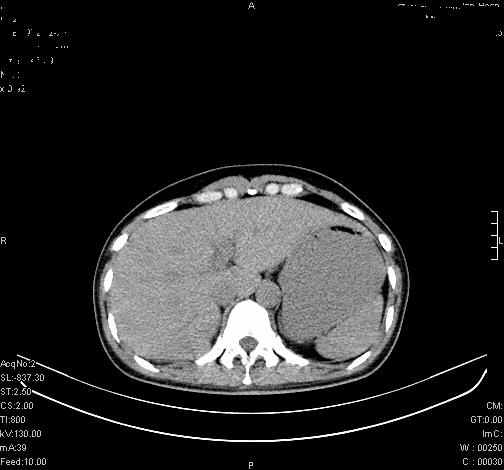

标题: CL0340:【】肾上腺囊肿,比较典型。

患者为年轻女性,查体发现右侧肾上腺囊性占位。无临床体征。

这么漂亮的图像,一看一目了然。典型的右侧肾上腺囊肿,周围有钙化。感谢搂主!

这么明显的弧形钙化,多考虑包虫病所致的寄生虫性囊肿。

右侧肾上腺囊性密度灶囊壁有钙化。考虑肾上腺囊肿,结核?

右侧肾上腺囊肿,周围有钙化。